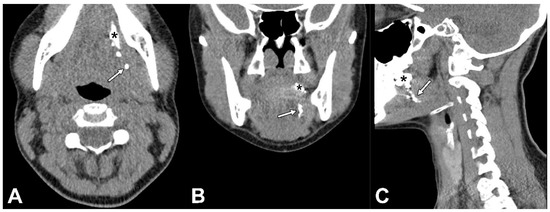

Figure 2.

Contrast-inverted dynamic X-ray images acquired 10 min following peritumoral injection of Lipiodol® in a patient with cT1N0 OSCC on the left side of the oral tongue (patient 6). No lymphatic drainage of Lipiodol® was observed with dynamic X-ray. (A) Anterior–posterior odontoid projection; (B) anterior–oblique odontoid projection; (*) injection site.